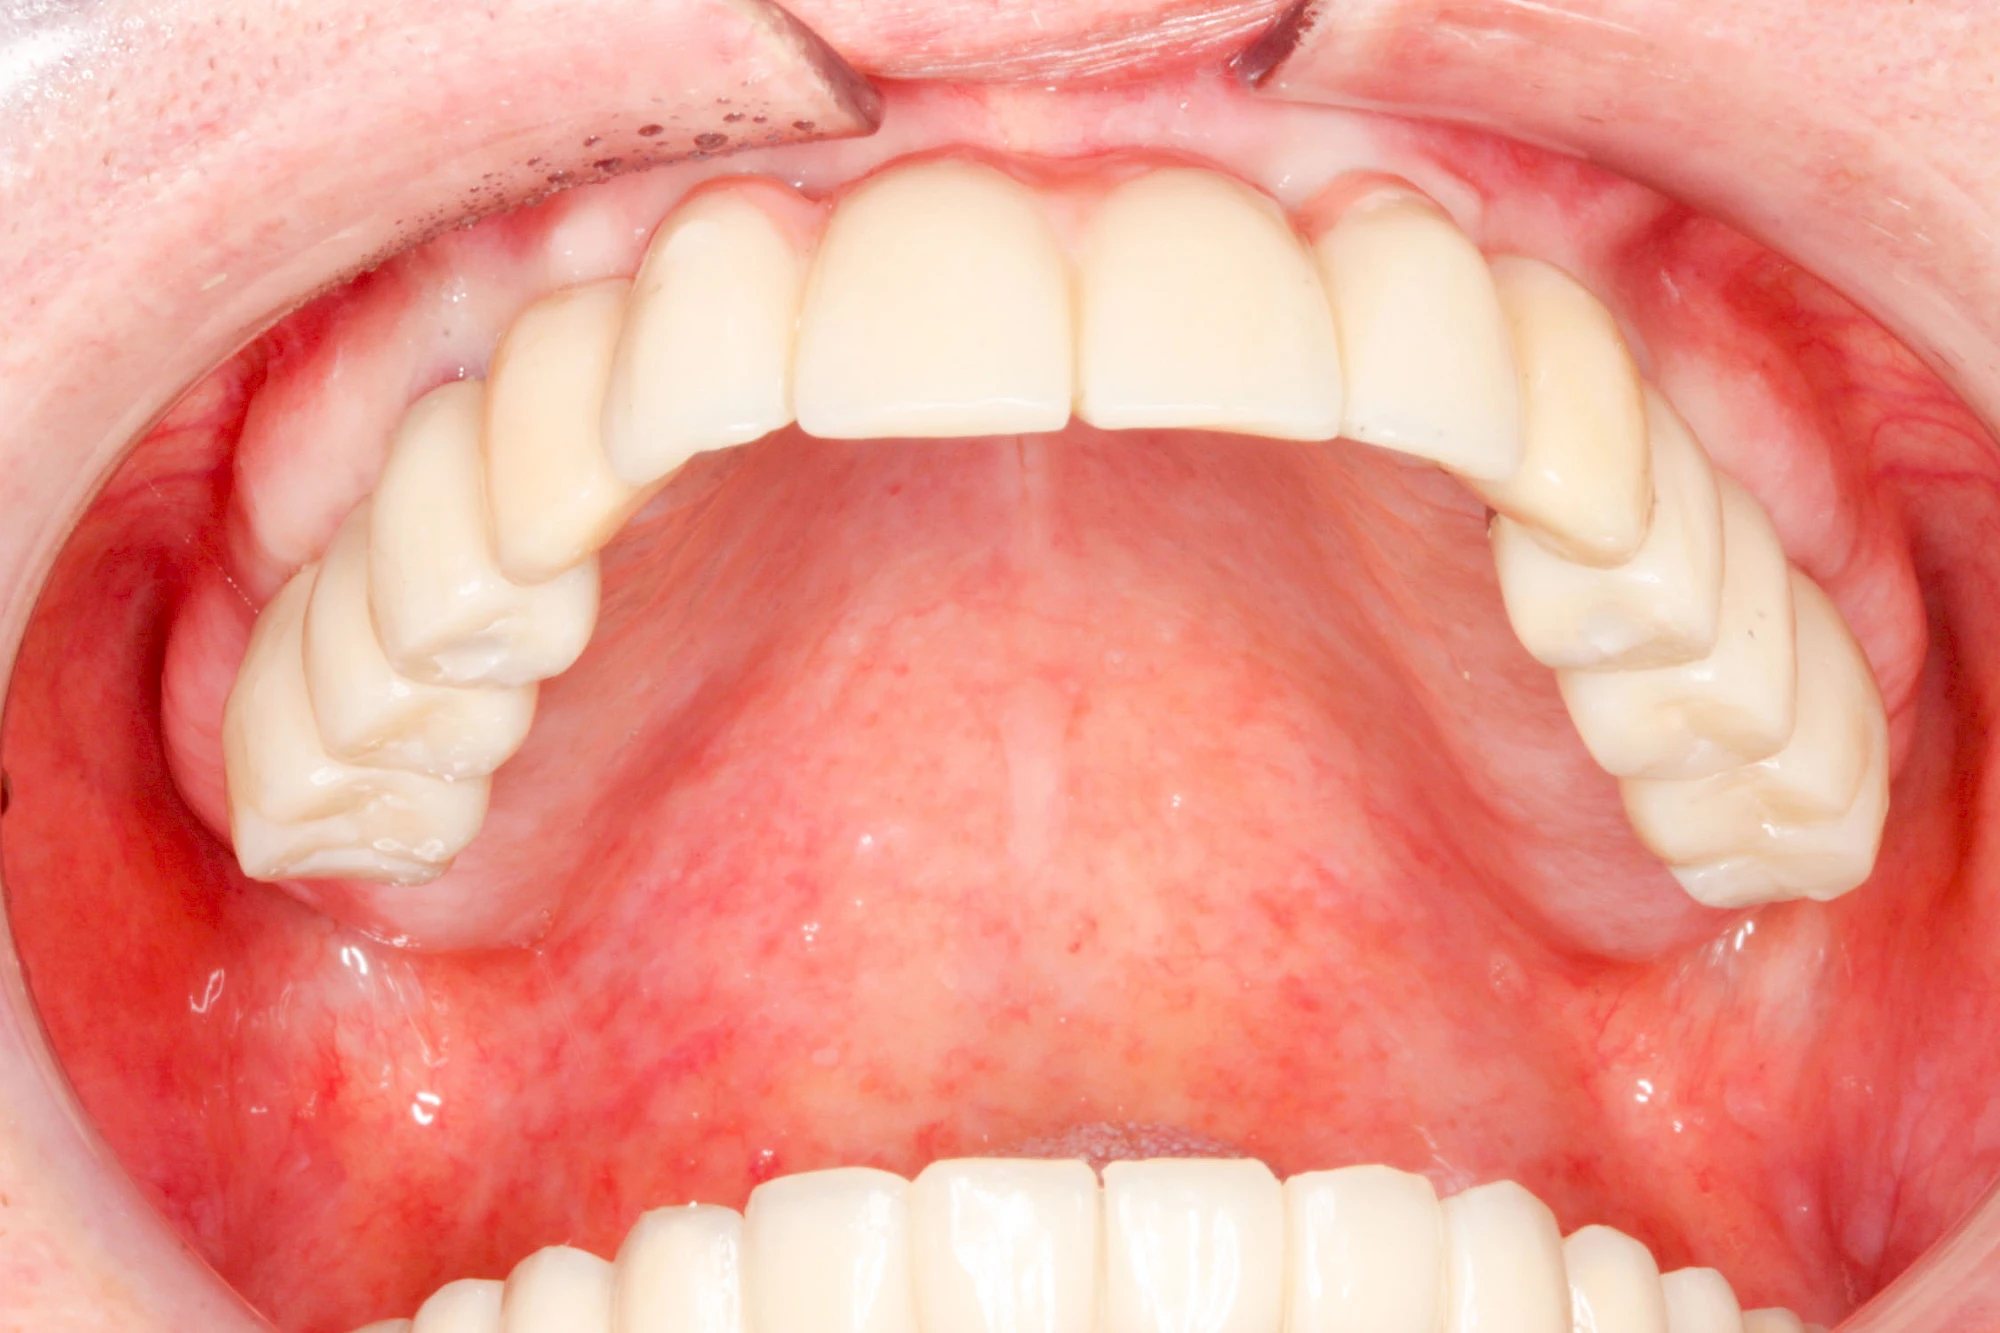

Implantate: Kronen & Brücken

Fehlen einzelne Zähne und die Nachbarzähne sind unbeschadet oder gut zahnärztlich versorgt, werden immer häufiger Implantate gewählt, um die Lücken zu schließen. Auch bei größeren oder verteilten Lücken, wenn keine herausnehmbare Prothese gewünscht ist, werden Implantate für Kronen- bzw. Brückenversorgungen gesetzt. In Einzelfällen entscheiden sich sogar zahnlose Patienten für eine festsitzende Versorgung auf Implantaten.

Varianten zur Verankerung von festsitzendem Zahnersatz auf Implantaten